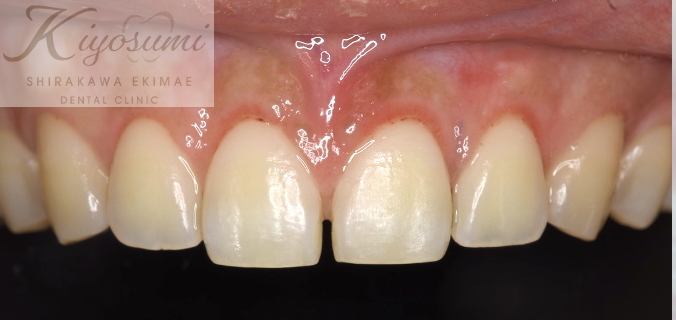

| 主訴 | 笑うと歯茎が目立ち、歯の長さが短い気がする。 |

| 治療内容 | デジタルワックスアップ、CTでシミュレーション後、歯冠長延長術を実施しました。 |

| 想定されたリスク | ※一度治療しても、長期経過で後戻りが起こるリスクがありました。 ※手術後、知覚過敏、歯肉退縮、後戻りが起こるリスクがありました。 |

お口とスマイル時のお顔のスキャンデータ、CTデータを重ね合わせて手術のシミュレーションを行い、歯の長さを出すために歯茎と骨を調整する歯冠長延長術を行いました。